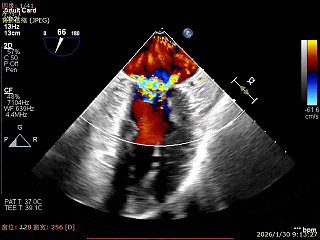

术前超声评估

经胸超声报告提示:患者二尖瓣2区及3区前叶关闭时脱入左房,二尖瓣重度反流(MR 4+),患者LA前后径约52mm,LVEDD约68mm,LVESD约42mm,EF值:65%,经胸超声测二尖瓣瓣口面积约6.1cm2,主动脉瓣无冠瓣脱垂并中重度反流,三尖瓣中度反流,估测中度肺动脉高压。

经食道超声精细化测量:肺静脉逆流,房间隔可穿刺高度约4.2cm,Flail宽度约21mm,Flail高度约8mm,Flail Gap约4mm, 3区AML长约23mm、PML长约12mm、2区AML约32.2mm,PML约16mm。

上Color,可见反流主要来自于3区

1区上Color,未见反流来源

2区上Color,可见反流来源

3区上Color,可见反流来源

3D Enface 可见反流由2区3区从前后冲出

房间隔可穿刺高度约4.2cm

Flail宽度约21mm,Flail高度约8mm

经胸短轴测得瓣口面积约6.1cm2

3区前叶长度约22mm,后叶长度约11.6mm

2区前叶长度约32.2mm,后叶长度约16mm

2区Flail Gap约4mm